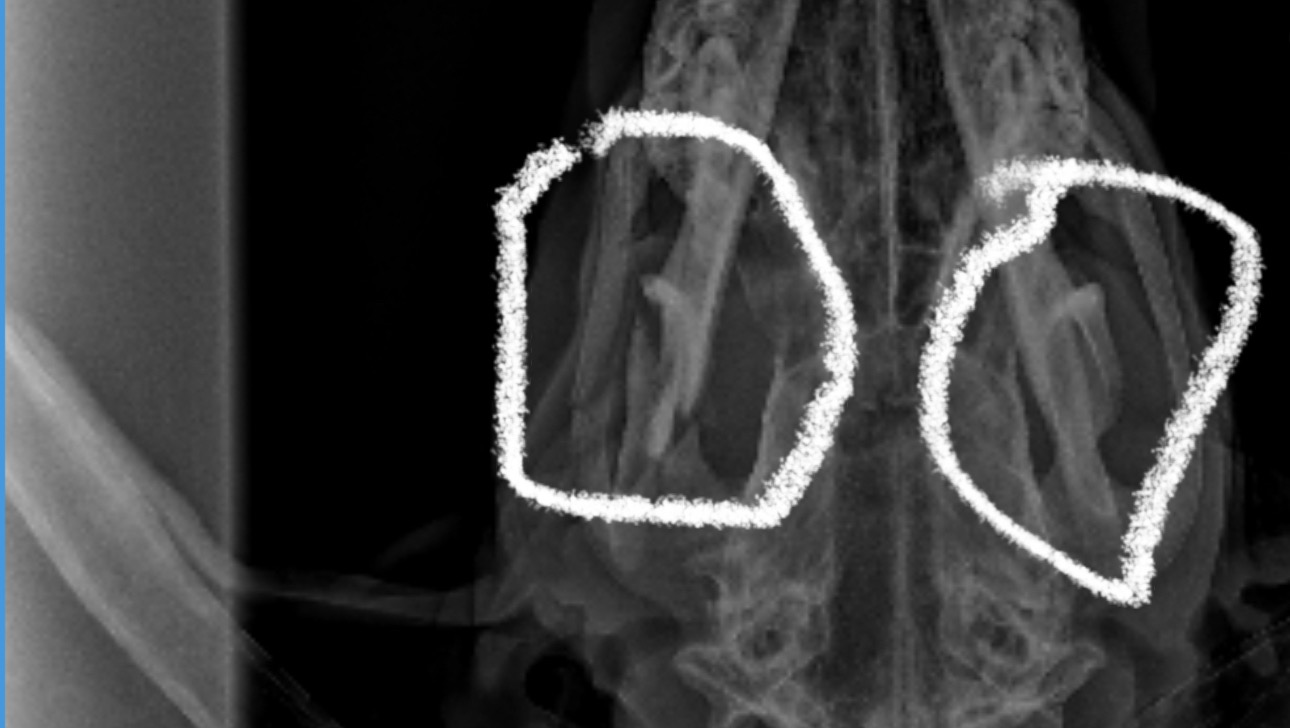

Our sweet boy Phantom our Doberman got hit by a car he suffered brain bleeding and a jaw fracture he needs some more scans and possible surgery for a full recovery which we cannot fully fund right now ,anything helps all of the money will be used for medications ,vet care and any surgeries moving forward to recovery